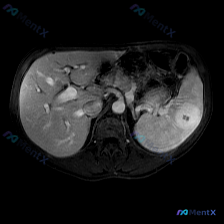

整理了一份有点意思的读片分析,核心是“关注点错位”——临床问的是脾脏病变,但影像的真正异常在肝脏。 一、先看影像基础信息 - 序列:腹部MRI轴位T1加权像 - 覆盖范围:上腹部(肝左/右叶部分、脾脏、胰腺体尾、胃泡、腹主动脉) - 图像质量:信噪比良好,无明显运动伪影 二、关键影像表现(按事实优先...

今天整理了一个挺有意思的影像读片病例,有点「答非所问」但非常考验临床思维,和大家分享一下思路。 --- 病例背景与影像资料 用户明确问的是「脾脏病变」,提供的是一张腹部MRI-T2加权轴位图像。 先直接说针对「脾脏」的第一判断: 👉 在这张图像上,脾脏实质信号均匀,皮髓质分界清晰,没有看到局灶性的高...